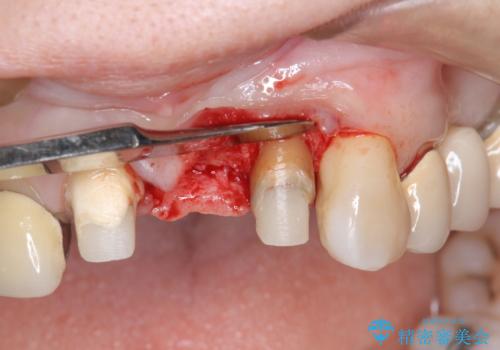

歯肉縁下カリエスも認められるため、挺出を行いセラミックブリッジを審美的に新製します。

虫歯が深くなった場合、挺出や歯周外科を行い歯周組織の状態を改善することでより安定した状態で予知性の高いセラミックブリッジを製作することが可能となります。